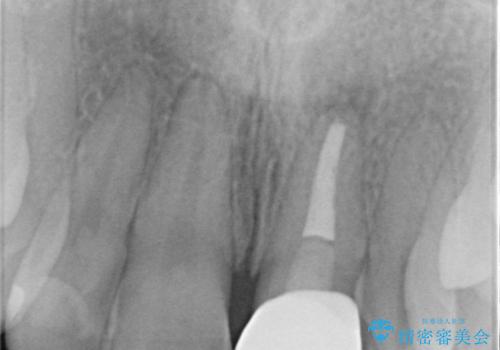

X線検査の結果、変色をきたしている歯は根尖病変が存在し、神経が失活している状態でした。

根管治療を行ったのち、セラミッククラウンで審美性を改善していきます。